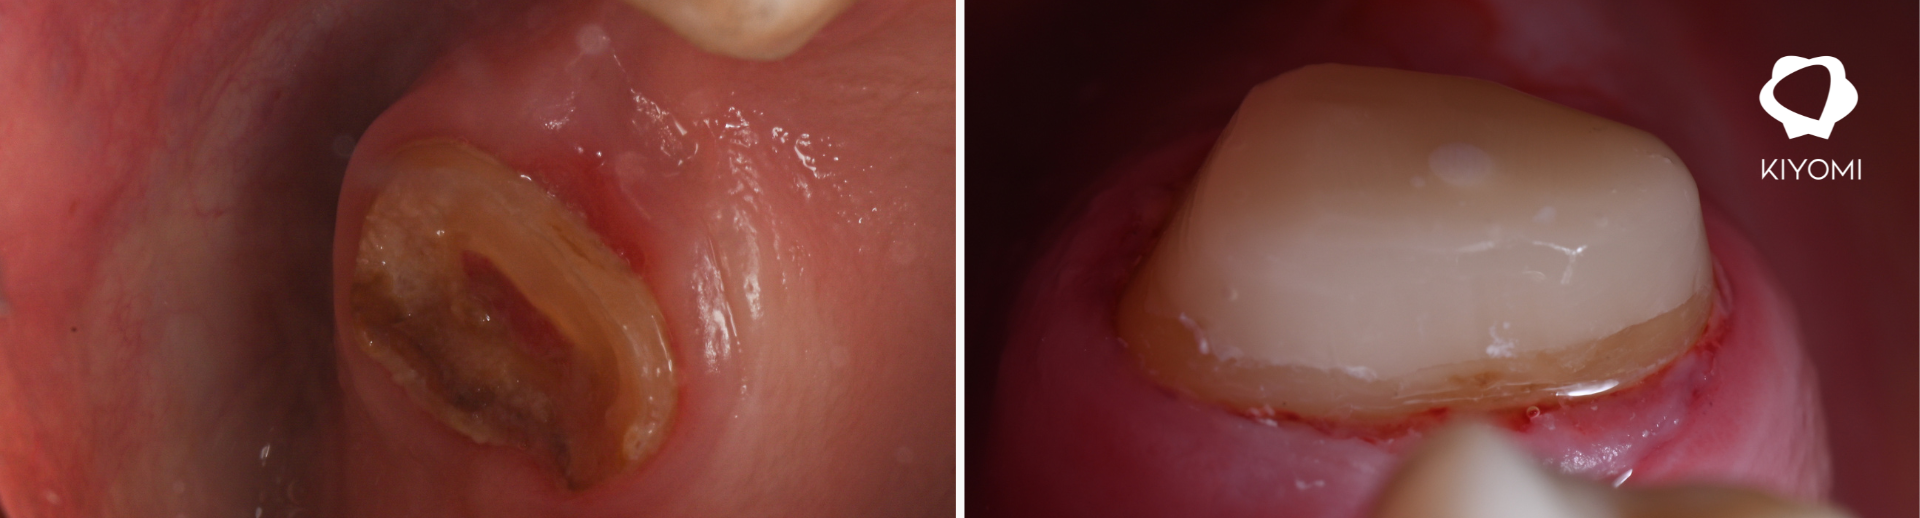

La rehabilitación del sector posterior supone uno de los mayores retos en odontología restauradora, especialmente cuando un diente debe asumir la función de pilar en una prótesis fija. En este caso clínico, el Dr. Francisco Monzó aborda la restauración de una zona edéntula en el maxilar superior (26), utilizando la U.D. 27 como pilar fundamental para un puente 25–26–27, mediante una combinación de endodoncia, poste de fibra y reconstrucción del muñón.

El paciente presentaba una ausencia dentaria en la posición 26, con necesidad de rehabilitación funcional y estética. La pieza 27, comprometida estructuralmente, requería un tratamiento endodóntico previo para poder garantizar su viabilidad como pilar protésico. La planificación del caso se centró en lograr una base sólida, priorizando la estabilidad del conjunto mediante un correcto efecto férula y una reconstrucción fiable del muñón.

Bajo aislamiento absoluto, se llevó a cabo la endodoncia de la pieza 27. Una vez finalizado el tratamiento, se preparó el conducto palatino dejando el espacio adecuado para la cementación de un poste de fibra de vidrio. Este paso es clave para reforzar la estructura interna del diente y mejorar la distribución de fuerzas.

El resultado es un build-up sólido que optimiza el efecto férula circundante, mejorando significativamente la resistencia del diente frente a cargas funcionales. Esta estabilidad es esencial para garantizar el éxito a largo plazo de la rehabilitación protésica en el sector posterior.